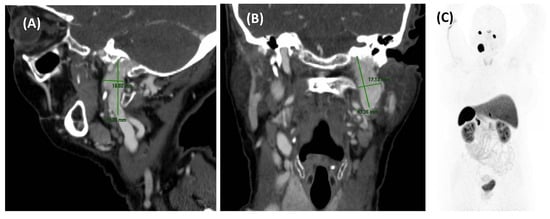

Usually, the initial clinical presentation of a paraganglioma is PT, which worsens with physical activity and does not change with compression of the jugular vein or occipital artery. A pulsatile red mass may be visible behind the tympanic membrane during otoscopy in patients with tumors affecting the tympanic cavity. Imaging studies should include a CT scan, which typically reveals a rounded soft tissue mass in the middle ear along the cochlear promontory, characteristic of tympanic paragangliomas. In larger paragangliomas (jugular or jugulotympanic), CT often shows bone erosion of adjacent structures. MRI with gadolinium contrast typically demonstrates an intensely enhancing mass, with larger tumors showing a distinctive heterogeneous “salt and pepper” appearance on T2 images (Figure 8, Figure 9 and Figure 10) [3,4,5,10,37].

Treatment for strictly tympanic paragangliomas is surgical, often requiring preoperative angiography with embolization to prevent significant bleeding. In some cases, radiotherapy effectively controls tumor growth, particularly in cervical paragangliomas. Depending on the stage of the disease, treatment may involve resection, embolization, external radiotherapy, or systemic radionuclide therapy [3,10,12,37].